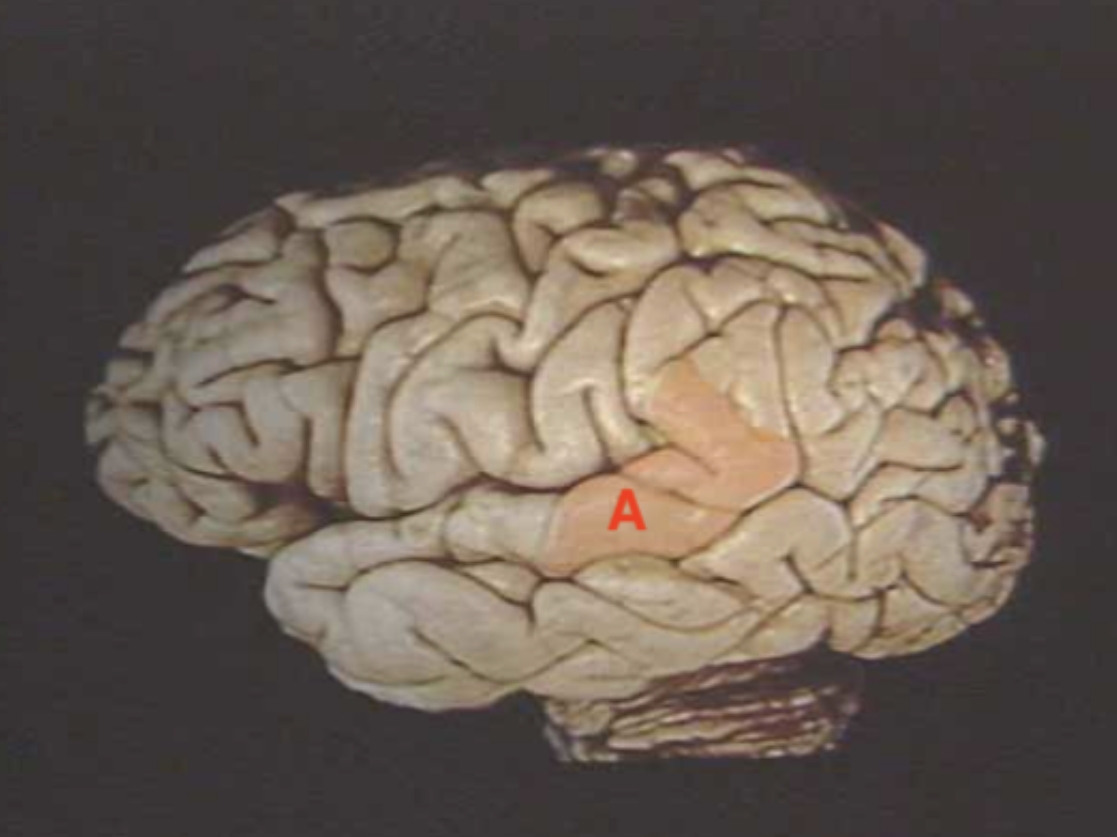

A

Broca’s Area